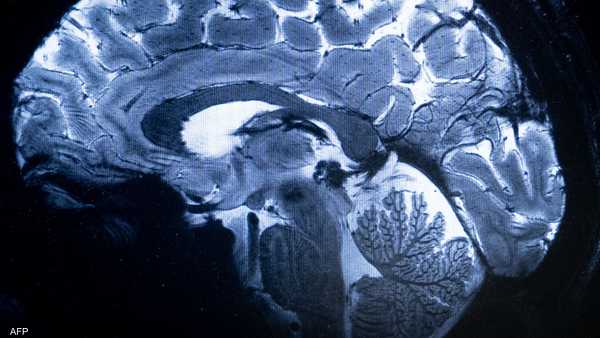

دراسة جديدة: مخ الانسان يغتسل أثناء النوم

على مدار عقود طويلة، ظل العلماء يفكرون في مشكلة أساسية، وهي كيف يتخلص مخ الانسان من النفايات التي يفرزها أثناء العمل والتفكير طوال اليوم، والتي تتضمن بروتينات وجزيئات زائدة قد تتحول إلى مواد سامة في حالة عدم التخلص منها، ومن بينها بروتينات الأميلويد بيتا وتاو التي تعتبر من المسببات الأساسية لمرض الزهايمر.

وفي عام 2012، توصل فريق بحثي بجامعة روشستر الأميركية برئاسة اخصائية طب الأعصاب مايكن نيدرغارد إلى وجود نظام دوري لم يكن معروفاً من قبل لطرد الفضلات السامة من المخ.

وتبين من خلال أبحاث على فئران التجارب تدفق السائل النخاعي داخل أنفاق حول الأوعية الدموية في المخ، حيث تمر هذه القنوات على نوعية من خلايا المخ تعرف باسم الخلايا النجمية وتختلط بما يعرف باسم “السوائل الخلالية”، حيث تقوم بجمع الفضلات وتحملها خارج المخ عبر المساحات حول الأوعية الدموية.